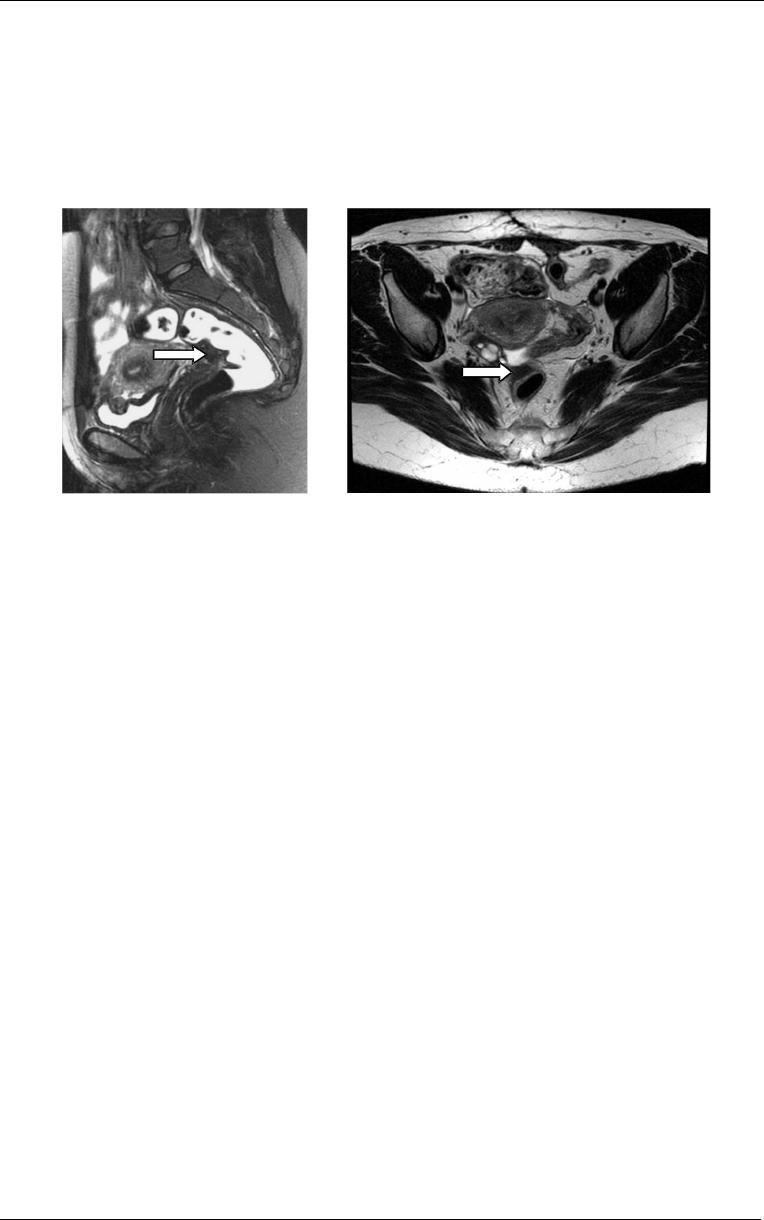

Utilizando a ressonância magnética para o diagnóstico do envolvimento da

parede intestinal por endometriose profunda (Fig. 9 e 10), Dumontier et al (2000)

encontraram sensibilidade de 75% e especificidade de 100%. Para a determinação

da sensibilidade, especificidade e valores preditivos positivo e negativo do método no

diagnóstico do comprometimento da parede retal, Camagna et al (2004) obtiveram

valores de 53%, 82%, 69% e 69%, respectivamente, enquanto os resultados de

Chapron et al (2004) foram de 76,5%, 97,9%, 96,3% e 85,2%.

Figura

9

- Imagem de

ressonância magnética em corte

sagital evidenciando

deformidade e espessamento do

reto (seta) decorrente de

endometriose intestinal. Obs:

Imagem cedida pelo Dr. Dario

Tíferes do Laboratório de

Análises Clínicas Gastão Fleury

S/C Ltda.

10

- Imagem de ressonância magnética

em corte axial, evidenciando espessamento do

reto (seta) decorrente de endometriose

intestinal. Obs: Imagem cedida pelo Dr. Dario

Tíferes do Laboratório de Análises Clínicas

Gastão Fleury S/C Ltda.